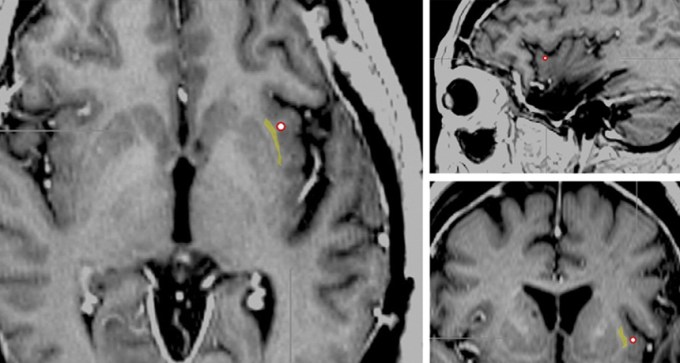

Electrode turns consciousness on and off

Woman lost awareness, though appeared awake, when her brain was stimulated near an area called the claustrum.